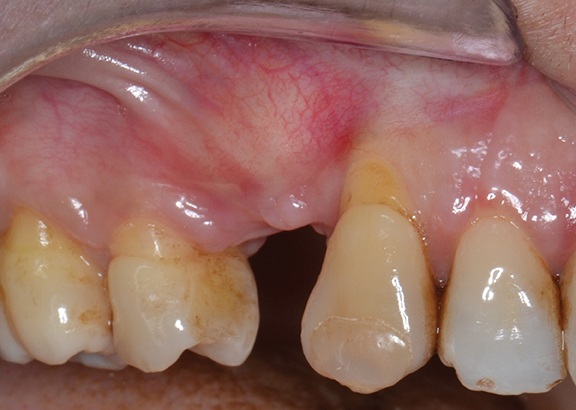

A 52-year-old female patient, classified as ASA I, presented with a localized ridge atrophy in the right maxillary quadrant as a result of a previous extraction of the maxillary first premolar that precluded implant placement (Fig. 1).

Fig. 1: Intraoral view of the edentulous site

A full-thickness trapezoidal flap was elevated to expose the recipient site (Fig. 4). After releasing all muscular attachments, flap extension was checked coronally (Fig. 5).

Fig. 4: Intraoral view of the atrophic bone area

Block by Block